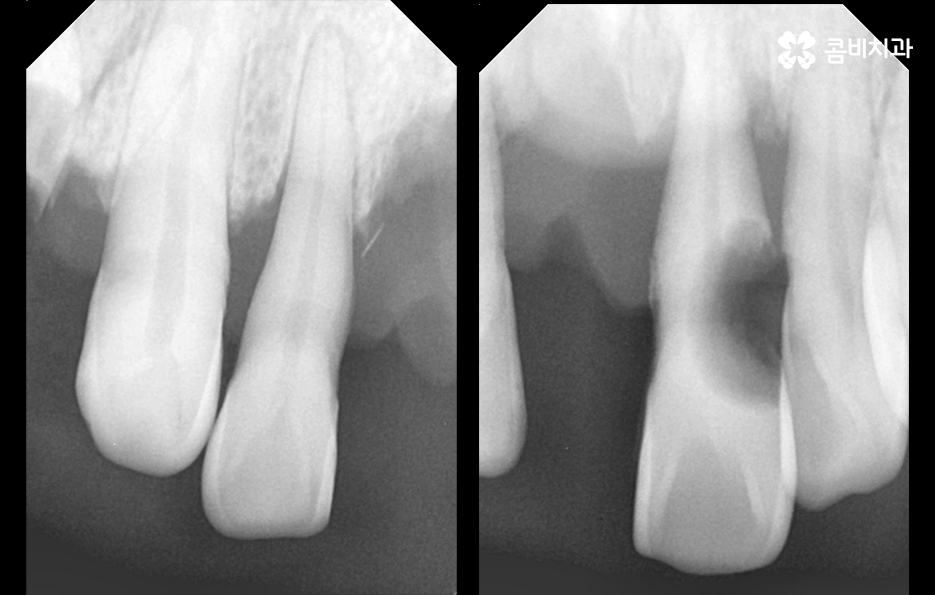

위 환자분의 엑스레이 사진을 보면 치아의 뿌리 부분에 가깝게 잇몸이 내려앉은 것을 볼 수 있는데 치아의 구조에서 뿌리쪽은 법랑질이 없기 때문에 잇몸이 내려앉고 잇몸 뼈가 치주염으로 녹게 되면 치아가 너무 아파서 식사를 하기에도 어렵고 물 한잔만 마셔도 이가 시릴 정도로 일상에 지장을 느끼실 수 있어요

결국 치아가 흔들릴 정도까지 잇몸 뼈가 녹고 치아의 뿌리도 함께 손상된다면 발치로 이어지겠지만 임플란트의 과정은 잇몸이 건강하신 환자분들과 잇몸이 약해지고 얇아지신 분들의 경우에는 치료적인 접근이 달라지기 마련인데 일반적인 임플란트의 경우 치아를 발치하고 임플란트를 올리기 까지 약 5~6개월 정도가 소요된다면 잇몸 뼈가 녹을 정도로 잇몸이 약해진 분들의 경우에는 뼈이식을 포함하여 경우에 따라서는 1년까지도 치료 기간이 걸릴 수 있기 때문에 임플란트 치료 역시도 어려운 과정을 겪게 될 수 있다는 점에서 치주염 발치의 경우 결코 가볍지 않은 시술 과정이 동반될 수 있어요